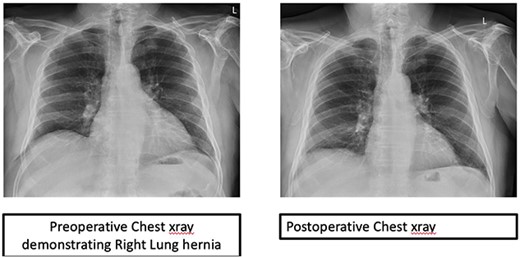

Over time, the bruising subsided, however he continued to have a bulge and localized pain. A CT scan of the chest revealed splaying of the eighth and ninth ribs with bulging of lung and perihepatic fat consistent with herniation (Fig. 1). He was referred to Thoracic surgery outpatient clinic for consideration of surgical management due to ongoing symptoms.

The patient had an uneventful recovery and remains asymptomatic with no recurrence after 6 months (Fig. 3).